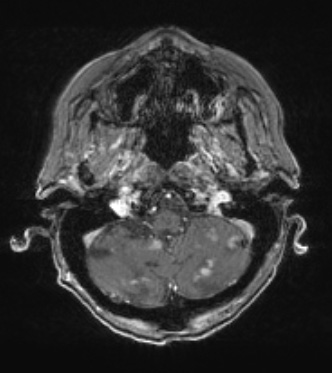

Cerebellar T1-weighted scan with applied contrast demonstrates numerous deep and superficial lesions.